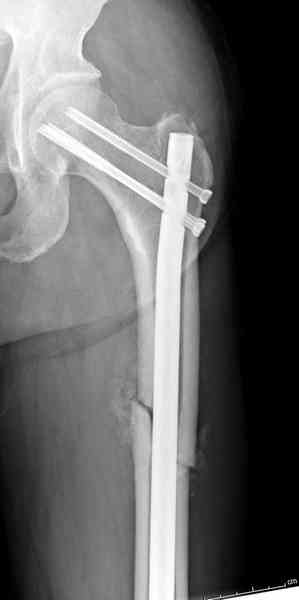

В операционной спереди гвоздя провел два 6.5 мм каннулированных шурупа, также через проксимальное отверстие антеградного гвоздя удалось провести шуруп.

При "ipsilateral femoral shaft and neck fractures" пользуемся ретроградным штифтом до малого вертеля, а шейку фиксируем каннюлированными шурупами в 6.5 или 7.3 мм в зависмости от диаметра шейки.

Здесь представлены снимки больного 65 лет, поступившего с диагнозом перелом

бедра после автоаварии.

В первый же день произведено антеградное штифтованием DePuy Trochanteric Nail.

На второй день (7) обнаружен пропущенный перелом,

и проведены шурурпы через и спереди штифта без удаления.

Послеоперационные снимки